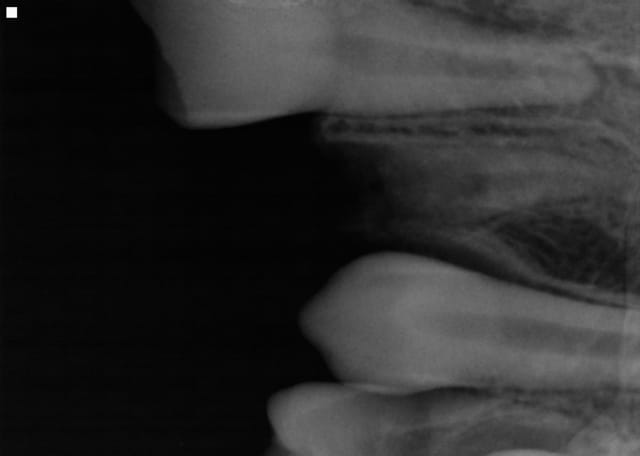

Historique: hier soir 18H coup de fil chez moi du parent d'un enfant de 12 ans, mon fils s'est cassé 3 dents en chutant. Donc je lui donne rendez vous ce matin.

Bilan: 11 21 fracturées mais la 22 est semi expulsée, collée à la gencive. Je me dis que je vais faire une réimplantation mais je découvre, en la prélevant, qu'elle a été fracturée . Reste donc la moitié de la racine que j'arrive à extraire avec une curette en laissant l'os et la racine intacte. J'ai traité le canal et recollé les deux morceaux et réimplanté.

Le plus urgent dans ce cas me semble être la préservation de la vitalité de 11 et 21.

A cet âge, les cornes pulpaires sont très proéminentes : une contamination a lieu très rapidement.

- Pour la 11 : il me semble voir une exposition de la corne pulpaire mésiale. A J+12h, j'aurai fait une pulpotomie de 1-2 mm pour cette corne et placé de la biodentine.

- Pour la 21 : une fracture juxta-pulpaire même sans exposition doit être recouverte dans les 24h. J'aurai placé un fond de CVI puis un composite.

- Pour la 22 : impossible de prédire avec certitude la suite. Une résorption externe est très probable avec une perte de la dent dans un délai de 6 mois à 6 ans.

Pour la contention, il me semble voir sur la radio un plot de résine entre 21 et 22. Cela ne tient jamais et saute rapidement dès que l'enfant mastique. Il aurait mieux valu une contention avec un fil souple qui solidarise des dents dans des plans différents : en l'absence des canines, contention de 4 à 4. Et alimentation molle sur une semaine.